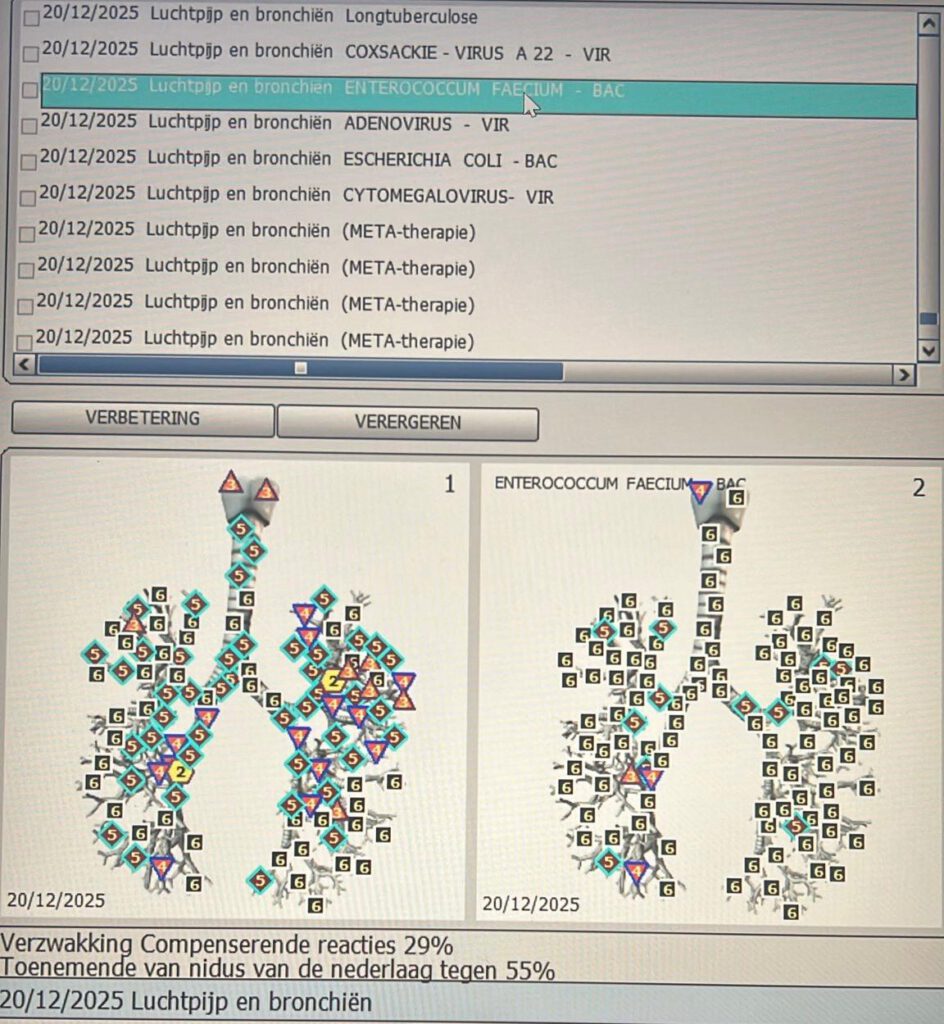

Hieronder een voorbeeld van een behandeling van de luchtpijp en bronchiën van een cliënte:

Hier links op de afbeelding zie je de luchtpijp en bronchiën zonder bacterie, dus hoe deze nu in originele staat zijn.

Je ziet hier dus al een aantal behoorlijke verzwakkingen.

Je ziet dit aan de grote hoeveelheid zesjes en vijven, maar ook behoorlijk wat vieren.

De tweeën en drieën die je ziet, zijn uiteraard wel goed!

Rechts zie je zelfde afbeelding maar dan met de bacterie.

Je ziet dat de luchtpijp en bronchiën behoorlijk verzwakt worden door de bacteriën, want je ziet dus allemaal zessen en een aantal vijven en twee vieren en slechts 1 x een drie!

Hieronder zie je nog in percentages de verzwakking aan de linkerkant (dus met bacterie) en de versterking aan de rechterkant na behandeling met meta-therapie.

De verzwakking is 29%, de versterking is 81%, dus totaal een verbetering van maar liefst 110%.